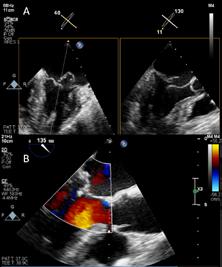

Ecocardiografia poate determina evaluarea fracției de ejecție a ventricului stâng (FEVS) ce permite distribuirea pacienților cu IC în una din clasele din cadrul clasificării funcționale NYHA. Ecocardiografia oferă și informaţii despre parametri precum: dimensiunile cavitaţilor cardiace - hipertrofie de ventricul stâng (HVS) excentrică sau concentrică, anomalii ale mișcării peretelui regional (care pot sugera patologie coronariană subiacentă, sindrom Takotsubo sau miocardită), funcţia ventricului drept (VD), hipertensiune pulmonară, funcţia valvulară și markerii funcţiei diastolice.6

HFrEF sau HFpEF, subliniind astfel terapia individualizată în funcție de fracția de ejecție a ventricului stâng. Efectuarea ecografiei cardiace cu încadrarea corectă a paciențior în categoriile propuse de definiția universală a IC înseamnă extinderea populației care poate beneficia de tratament optim în funcție de fenotipul existent.4,15